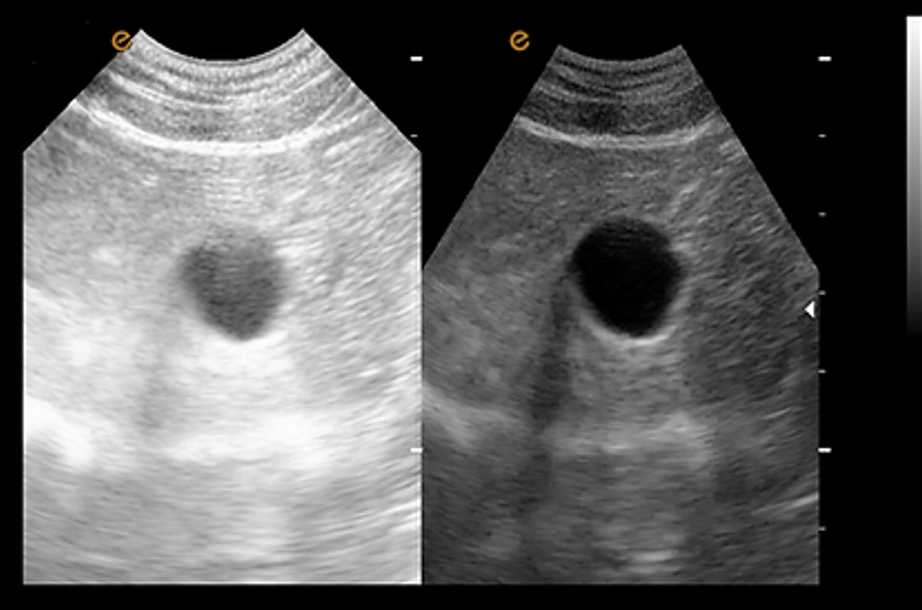

การถ่ายภาพขยาย ชุดหัวตรวจแบบอาร์เรย์นูน (Convex Array Probe) รองรับการถ่ายภาพขยาย ซึ่งช่วยขยายขอบเขตการสแกนของหัวตรวจอย่างมีประสิทธิภาพ ตอบโจทย์การใช้งานในด้านสูติศาสตร์, นรีเวชวิทยา และการวินิจฉัยที่ต้องการพื้นที่กว้าง รวมถึงการสังเกตสภาพของเนื้อเยื่อที่มีการบาดเจ็บและเนื้อเยื่อสำคัญ |